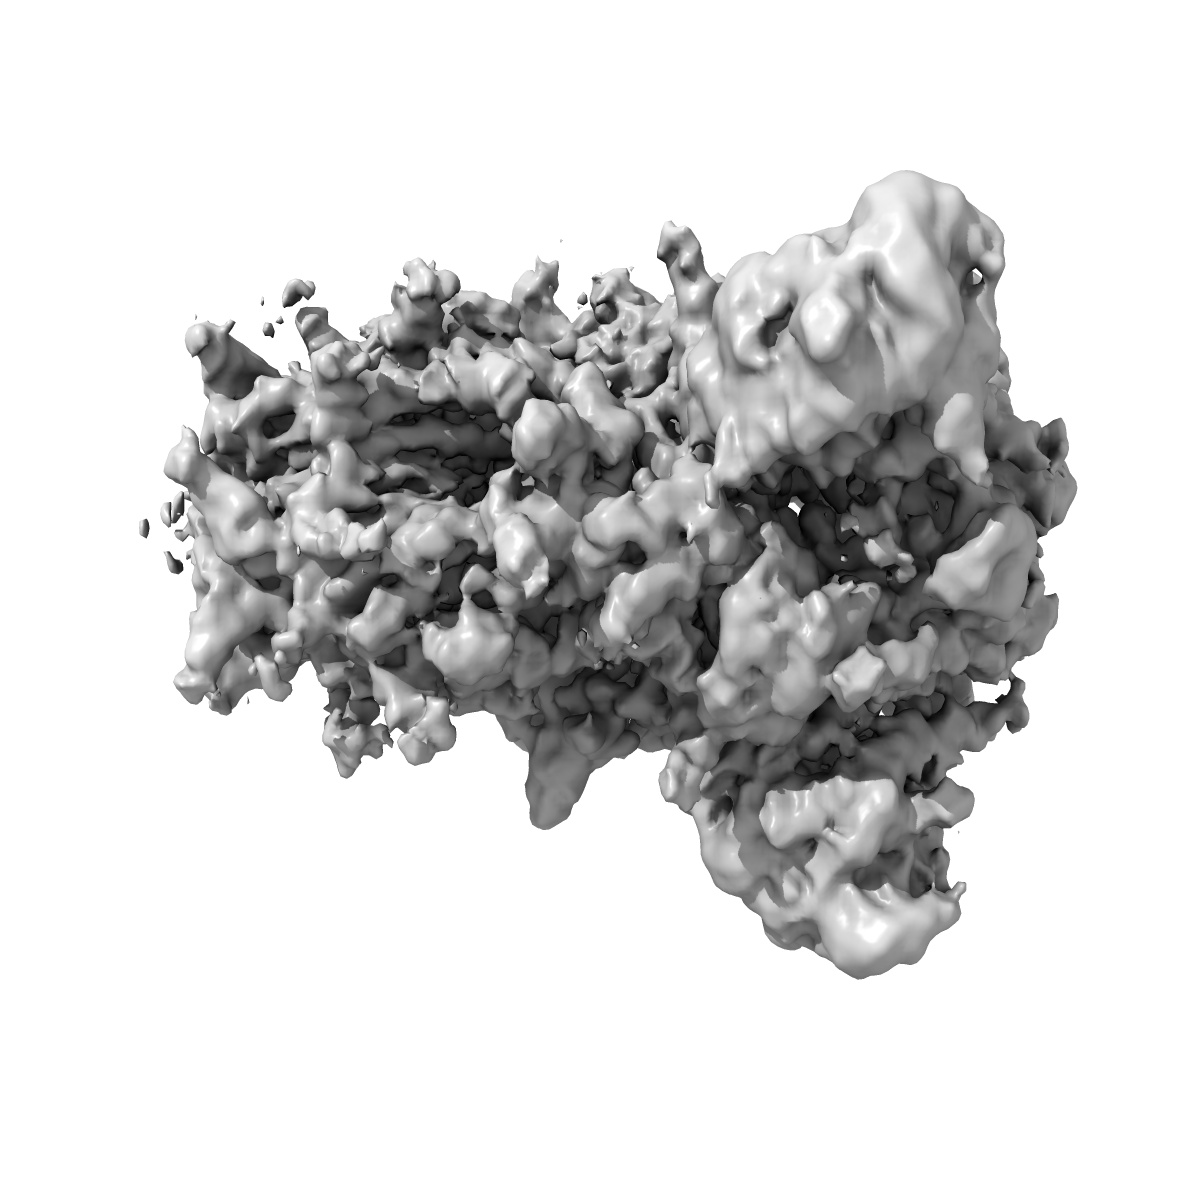

Structure of Disulphide-stabilized SARS-CoV-2 Spike Protein Trimer (x1 disulphide-bond mutant, S383C, D985C, K986P, V987P, single Arg S1/S2 cleavage site) in Locked State

Single-particle3.5 Å

Sample: Disulphide-stabilized SARS-CoV-2 Spike Protein Trimer

A thermostable, closed SARS-CoV-2 spike protein trimer.